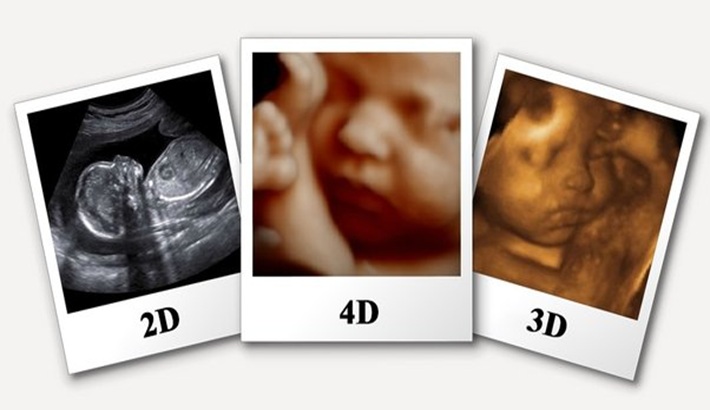

- رزولوشن بالای پروبهاپ: پروبهای جدید تصاویر واضحتری ایجاد میکنند و جزئیات کوچک بافتها را بهتر نشان میدهند.

- قابلیتهای تصویربرداری چند بعدی: دستگاههای سه بعدی و چهار بعدی تصاویر با عمق و جزئیات بیشتر ارائه میدهند که در بررسی جنین یا اندامهای داخلی مفید است.